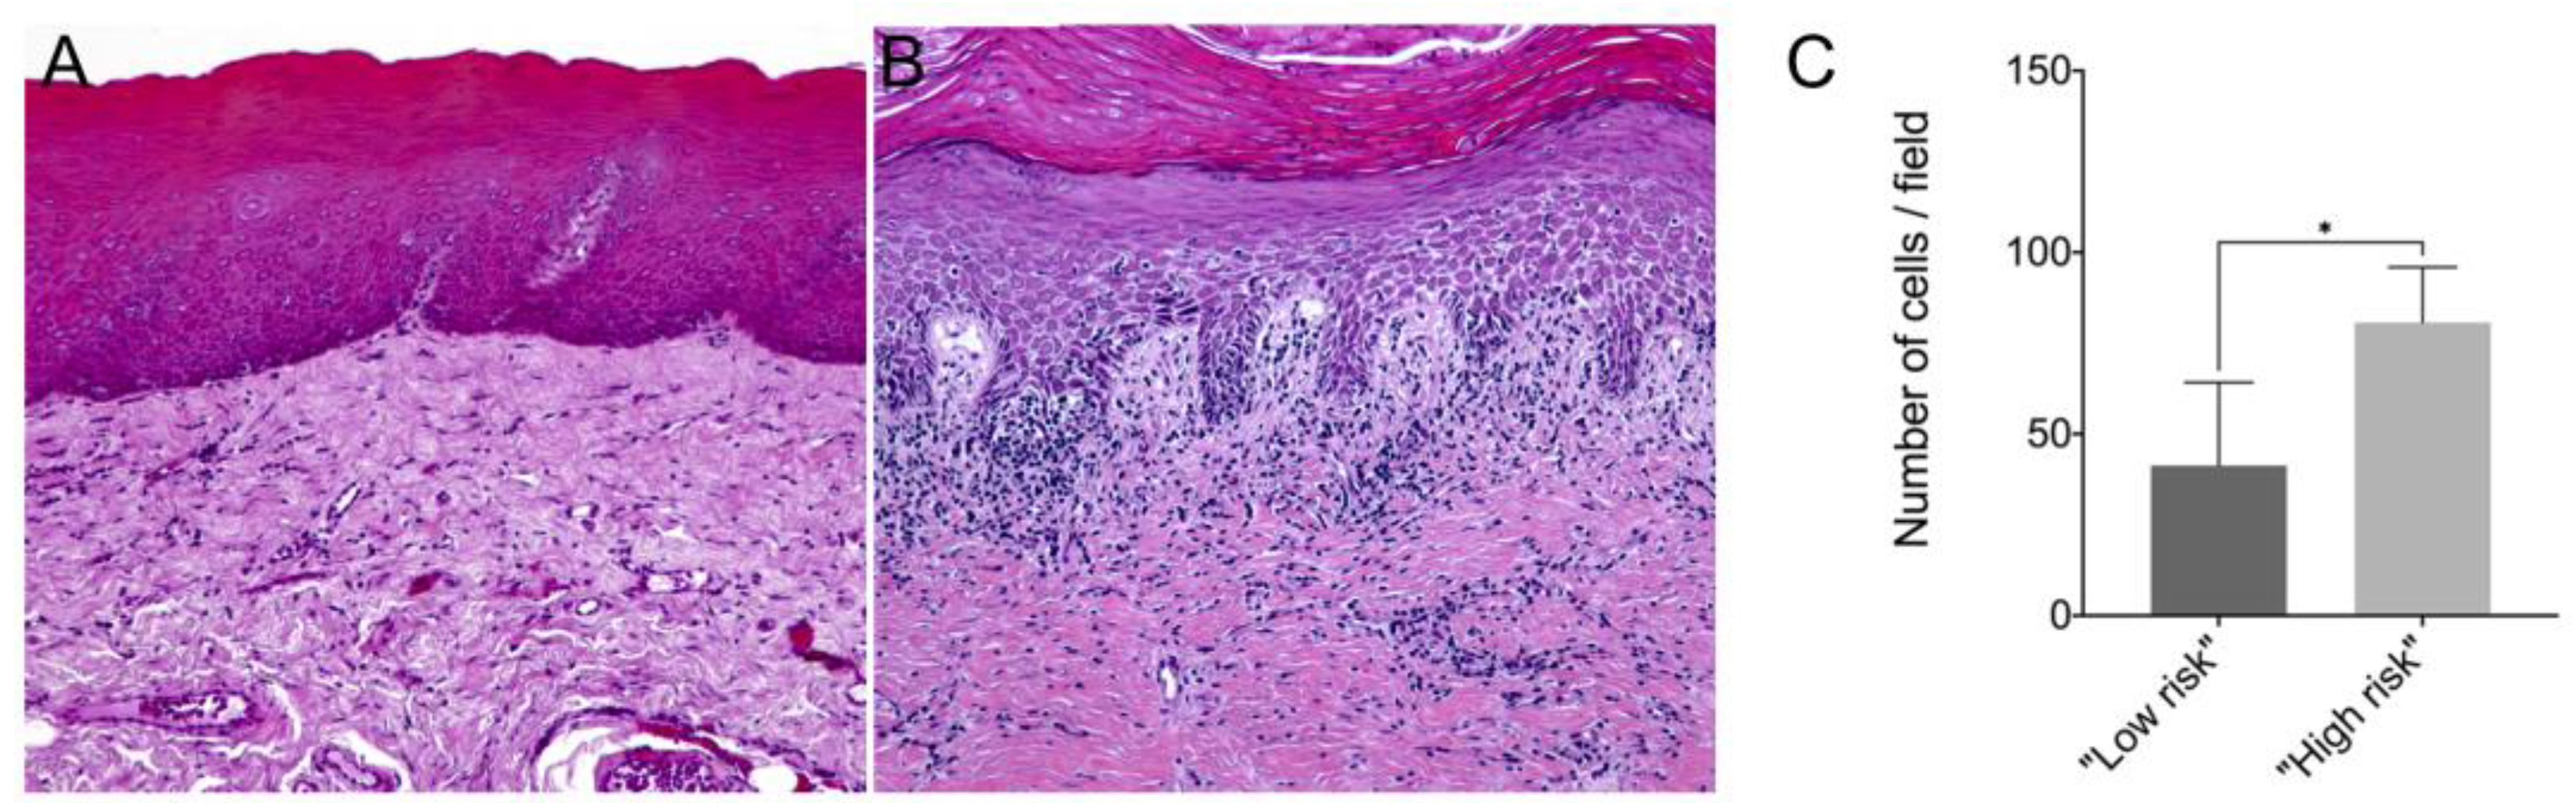

In this study, we showed that the frequency of subepithelial inflammatory cells was significantly higher in samples classified as “high risk” compared to “low risk” samples (95% CI: 0.000 to 93.20; p = 0.006), predominantly presenting a chronic lymphoplasmacytic inflammatory infiltrate (Figure 1). Furthermore, it has been demonstrated through immunofluorescence that dysplastic oral lesions exhibit hypoacetylation of H3K9 and low levels of γH2AX compared to the control group (IFH). Considering the H3K9ac intensity of labeling, there was a statistically significant reduction in H3K9ac levels between the “low-risk” (95% CI: 2854.89 to 6274.81; p < 0.001) and “high-risk” groups (95% CI: 467.65 to 3993.28; p = 0.01) compared to the control group as well as a significant reduction in H3K9ac levels between the low-risk and the high-risk group (95% CI: −3549.90 to −1118.87; p < 0.001). On the other hand, the percentage of H3K9ac positive cells in the intraepithelial area was lower in the “low-risk” group compared to the control group (95% CI: −30.61 to −4.45; p = 0.006). In addition, H2AX phosphorylation levels decreased in “high-risk” lesions when compared to “low-risk” lesions (95% CI: −0.76 to −0.06; p = 0.015) and control (95% CI: −1.50 to −1.97; p = 0.009). Figure 2 shows the representative images of H3K9ac and γH2AX immunofluorescence and graphics of quantitative analysis.

Figure 1. Representative image of hematoxylin–eosin (HE) staining from a (A) “low-risk” lesion biopsy and a (B) “high-risk” lesion biopsy; (C) Number of inflammatory cells per field in samples from “low-risk” and “high-risk” lesions. The mean number of immune cells counted per field in paraffin-embedded tissue samples of “low risk” and “high risk” lesions. * p < 0.05.